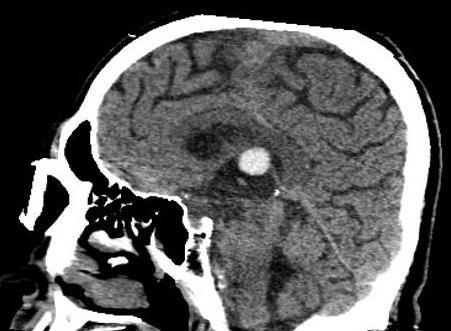

Nang keo não thất

» Thông tin: Nữ giới – 70 tuổi.

» Lâm sàng: Đau đầu.